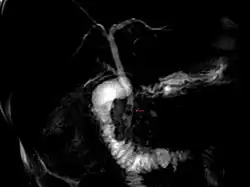

Magnetic resonance cholangiopancreatography (MRCP) image of two gallstones in the distal common bile duct

The diagnosis of choledocholithiasis is suggested when the liver function blood test shows an elevation in bilirubin and serum transaminases. Other indicators include raised indicators of ampulla of vater (pancreatic duct obstruction) such as lipases and amylases. In prolonged cases the international normalized ratio (INR) may change due to a decrease in vitamin K absorption. (It is the decreased bile flow which reduces fat breakdown and therefore absorption of fat soluble vitamins). The diagnosis is confirmed with either a magnetic resonance cholangiopancreatography (MRCP), an endoscopic retrograde cholangiopancreatography (ERCP), or an intraoperative cholangiogram. If the patient must have the gallbladder removed for gallstones, the surgeon may choose to proceed with the surgery, and obtain a cholangiogram during the surgery. If the cholangiogram shows a stone in the bile duct, the surgeon may attempt to treat the problem by flushing the stone into the intestine or retrieve the stone back through the cystic duct.

On a different pathway, the physician may choose to proceed with ERCP before surgery. The benefit of ERCP is that it can be utilized not just to diagnose, but also to treat the problem. During ERCP the endoscopist may surgically widen the opening into the bile duct and remove the stone through that opening. ERCP, however, is an invasive procedure and has its own potential complications. Thus, if the suspicion is low, the physician may choose to confirm the diagnosis with MRCP, a non-invasive imaging technique, before proceeding with ERCP or surgery.